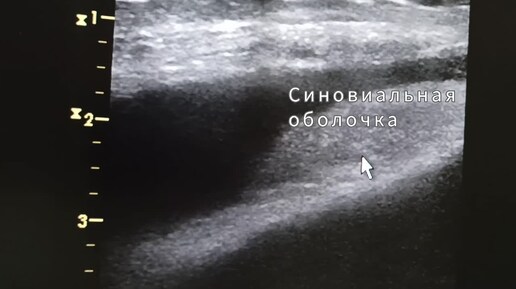

Начинающим врачам УЗИ: Супрапателлярный бурсит и синовит